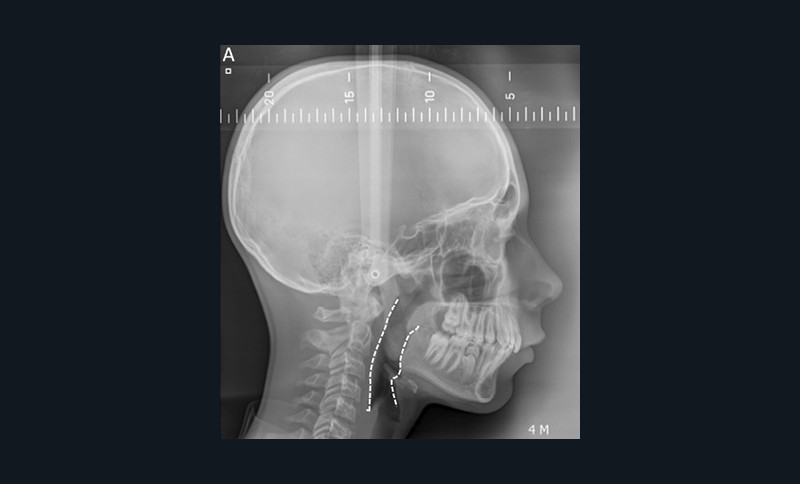

Examen radiologique

Certaines caractéristiques cranio-faciales sont associées aux troubles obstructifs du sommeil. La téléradiographie de profil évalue la présence d’un décalage squelettique antéropostérieur mandibulaire associé ou non à un décalage maxillaire. Au niveau céphalométrique, les enfants présentant un Sahos ont souvent un angle SNB diminué (rétromandibulie), un angle ANB augmenté (classe II squelettique) et une hyperdivergence faciale [5]. On peut également retrouver un abaissement de l’os hyoïde et une micromandibulie. La téléradiographie de face met en évidence une insuffisance maxillaire transversale principalement chez des patients avec une face longue et étroite et une ventilation buccale [5-9-11].

La téléradiographie de profil permet aussi, pour un praticien entraîné, d’objectiver les tissus mous des Voies aériennes supérieures (VAS), bien que leurs volumes soient mieux visualisés avec un Cone Beam Computed Tomography (CBCT) [12]. Un rétrécissement de la lumière du pharynx peut être rapproché d’un déficit squelettique et d’un risque plus élevé de Sahos. Kim et ses collègues ont proposé des mesures des voies respiratoires pharyngées, du palais mou, de la langue et de l’os hyoïde à l’aide de repères minimaux et de lignes de référence [13-14] (fig. 8).